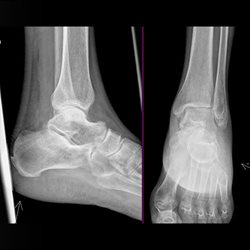

Various adult extremity cases. Shoulder, wrist, ankle, elbow.